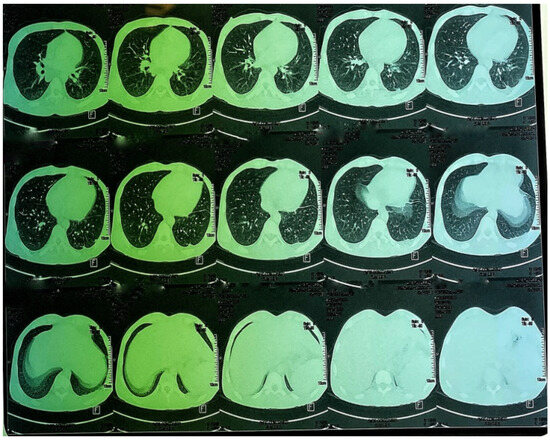

Figure 6. CT images of the thorax and abdomen:axial view.

Figure 7. CT images of the thorax and abdomen.

A CT scan of the chest, abdomen and pelvis was subsequently performed, showing a mild left pleural and abdominal effusion associated with right supra-diaphragmatic adenopathy and homogeneous hepatosplenomegaly (Figure 6 and Figure 7).